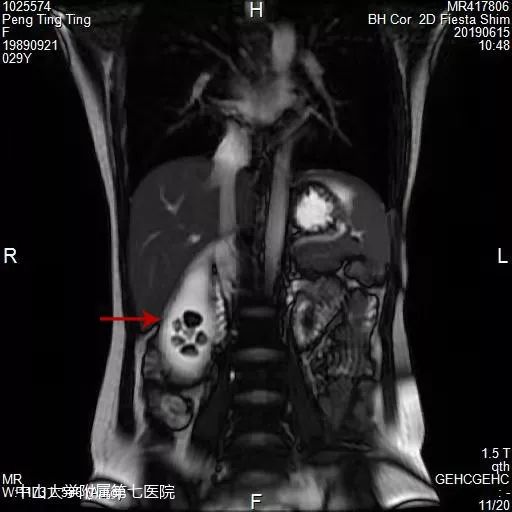

磁共振可见明显肿大的胆囊以及其内多发结石